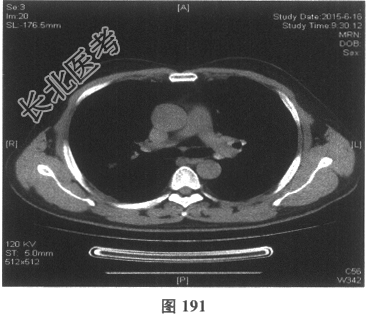

- 多项选择题4.[提示]患者应用多种抗生素治疗(第三代头孢菌素、青霉素加酶抑制剂)包括抗曲霉菌治疗无效,加用甲泼尼龙40mg静脉滴注病情好转。肺部CT检查显示病变明显改善。尿常规检查正常, 肾功能检测正常。复查肺部CT(图188~图195):示病变较前好转。Wegener肉芽肿的主要临床表现是( )